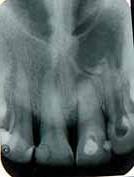

Radiographic evaluation of the involved tooth indicated a normal canal configurations of canals. (Figure 1)

Endodontic access was carried out under local anesthesia and rubber dam isolation. Four canals were detected following access preparation, two each in distal and mesial root. After debridement of the pulp chamber, some pulp tissue remained at the isthmus of mesial orifices. Further, careful probing in the isthmus area with an endodontic explorer revealed an intermediate canal. (Figure 2). Distal angulation working length radiograph showed three distinct canals mesially and two canals distally joiningat the apex. (Figure 3). All the five canals were negotiated and working length was determined. Cleaning and shaping was performed using crown down preparation with Profile nickel titanium rotary instrument (Maillefer, Dentsply), along with copiousirrigation of sodium hypochlorite and RC Prep (Premier,USA). On the second visit, master cone selection was made and obturated by lateral condensation procedure. The patient was recalled for check up and after a week, the tooth was restored with a permanent restoration. (Figure 4). The patient was followed up for two years.

Figure 1- Pre operative radiograph showing distal caries. Figure 2- Pulp chamber floor showing three independant mesial and two distal orifices. Figure 5- Pre operative radiograph showing mesial root and a distal root with an additional indistinct distolingual root. Figure 6- Pulp chamber showing three mesial and two distal canal orifices. Figure 7- Working length radiograph taken with distal shift technique. Figure 8- Post operative obturation radiograph showing three mesial and two separate distal roots. Figure 3 - Working length radiograph reveals three canals in the mesial root and two canals in the distal root. Figure 4- Post operative obturation radiograph.